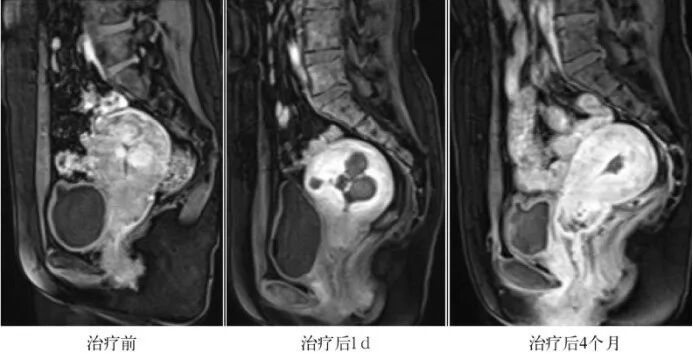

HIFU 治疗后,坏死的肌瘤逐渐被吸收,肌瘤缩小,子宫结构恢复正常(见图 2)

(图 2)